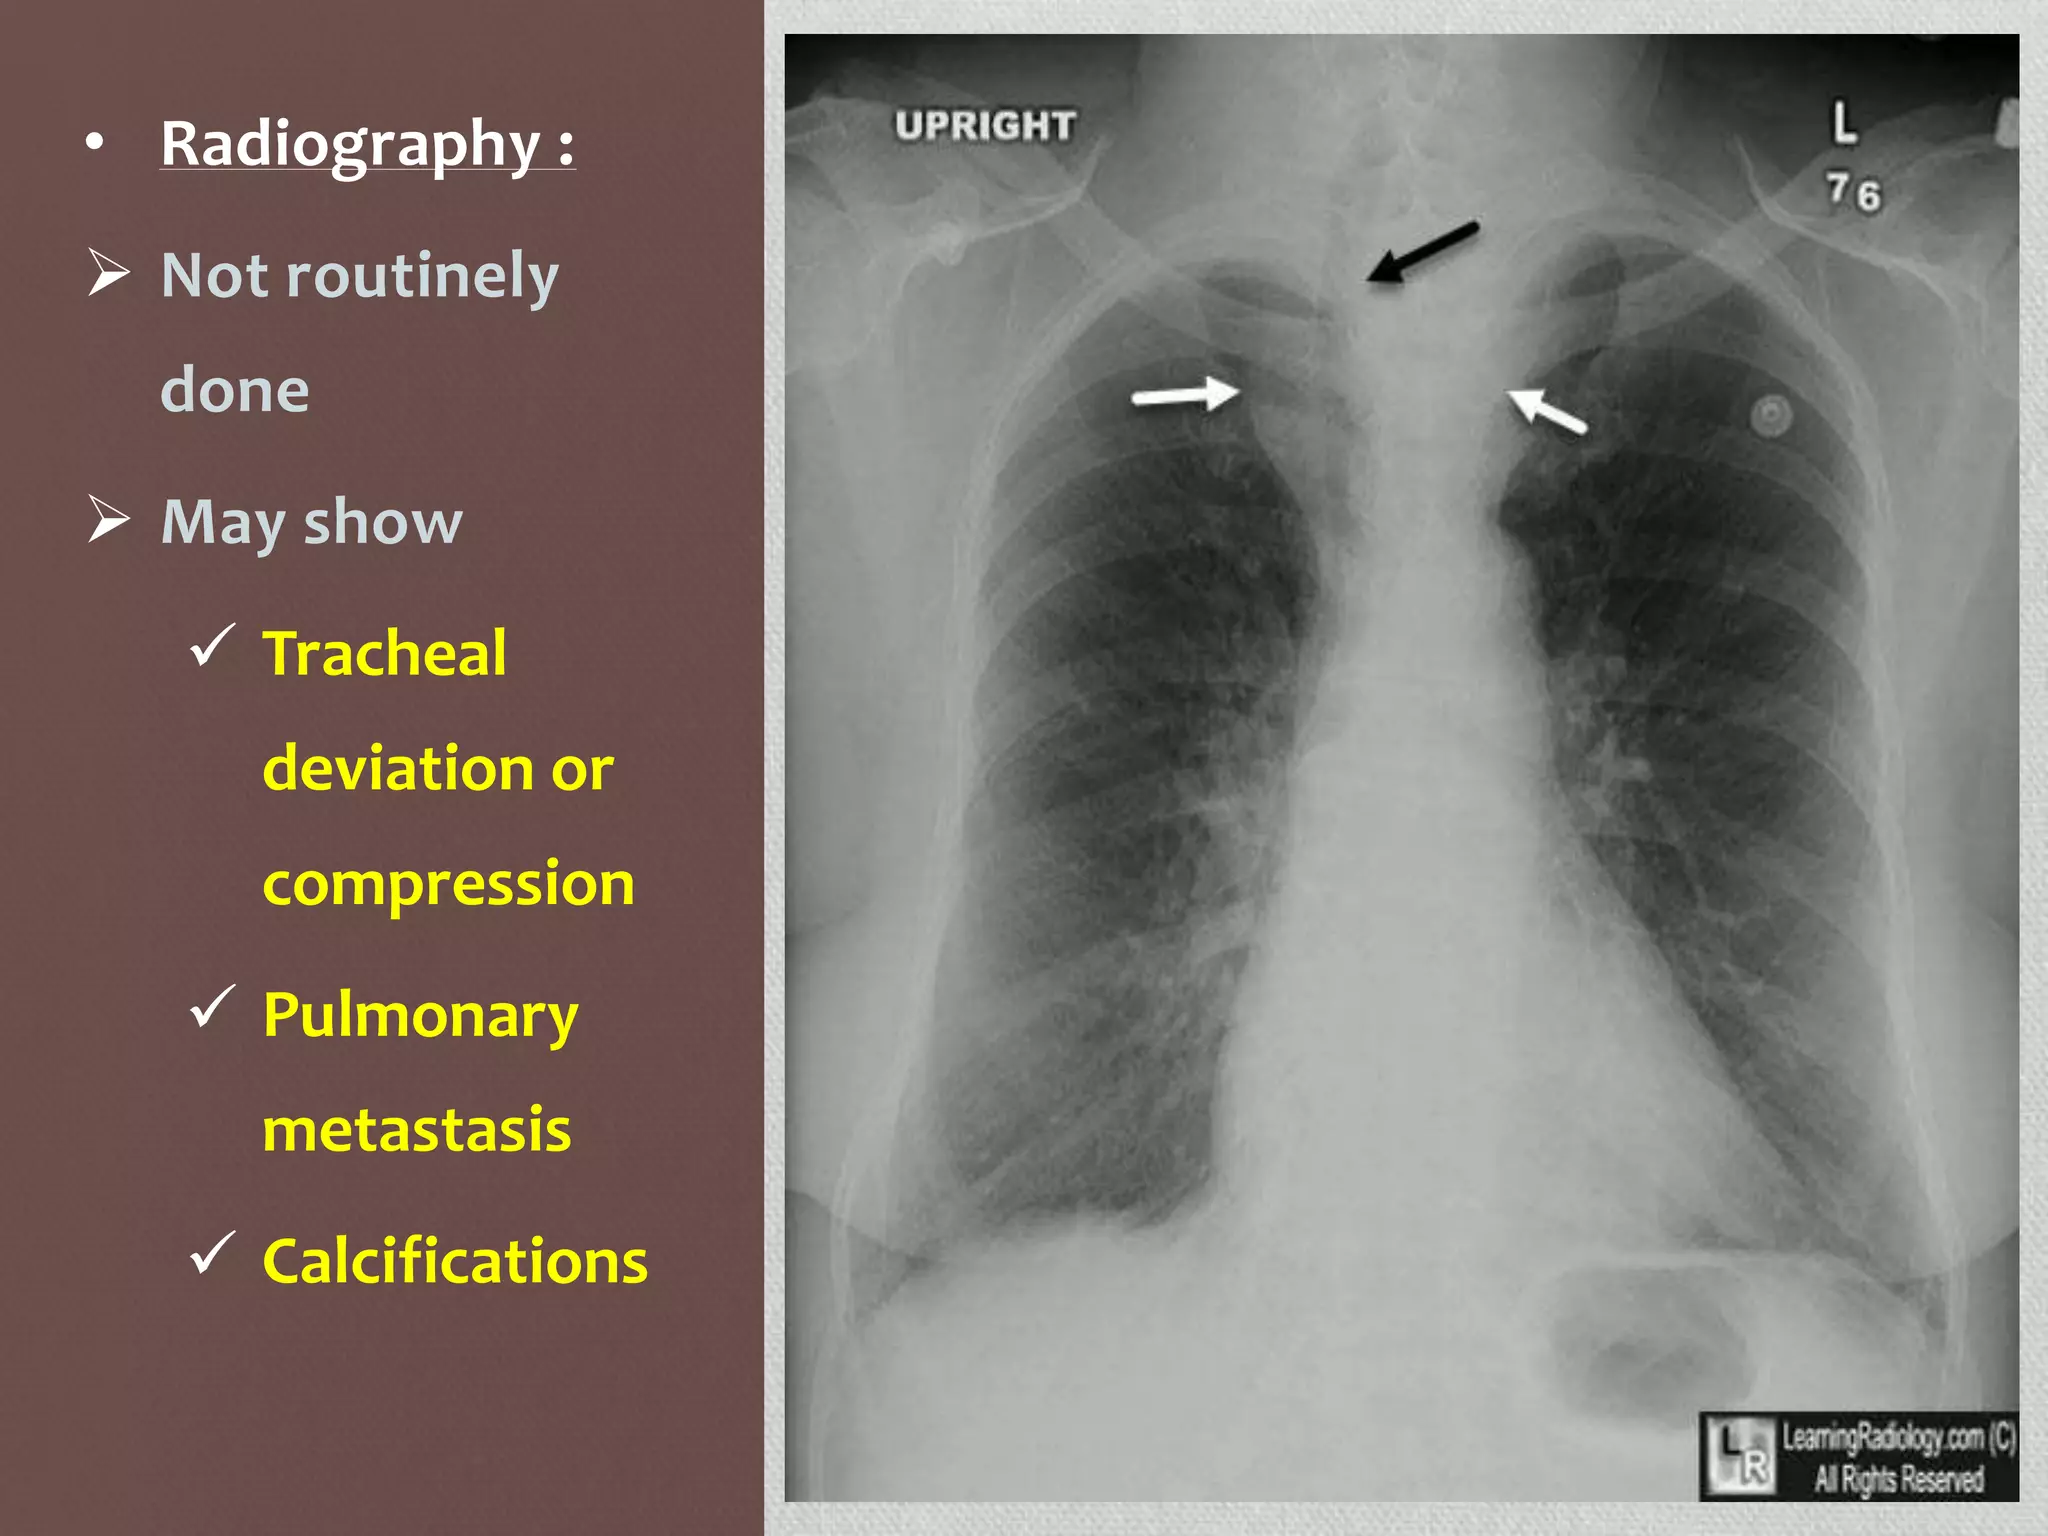

• Radiography :

 Not routinely

done

 May show

 Tracheal

deviation or

compression

 Pulmonary

metastasis

 Calcifications